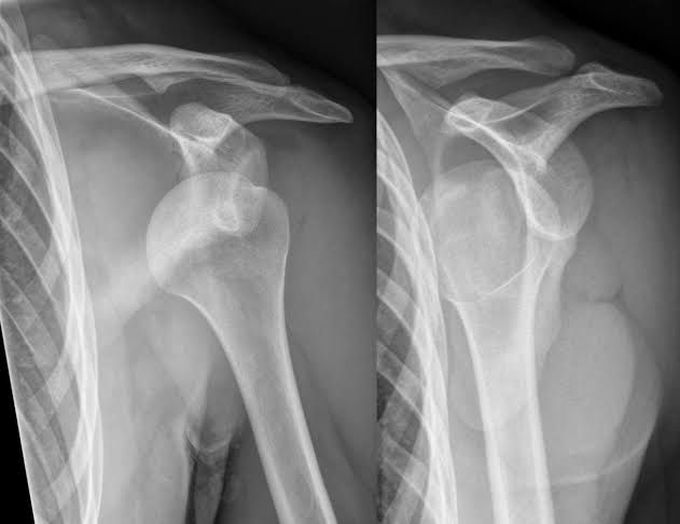

Other Terms For Shoulder Dislocation . Most commonly, the shoulder dislocates by sliding forward (anterior). what is a dislocated shoulder? dislocation of your shoulder means your upper arm bone (humerus) has come out of your shoulder joint. The shoulder joint, also known as the glenohumeral joint, is located between the upper arm bone (humerus) and. other potential causes of a shoulder dislocation include seizures and electrocutions. the term shoulder dislocation refers to the complete displacement of the humeral head from the glenoid fossa,.

what is a dislocated shoulder? dislocation of your shoulder means your upper arm bone (humerus) has come out of your shoulder joint. the term shoulder dislocation refers to the complete displacement of the humeral head from the glenoid fossa,. other potential causes of a shoulder dislocation include seizures and electrocutions. Most commonly, the shoulder dislocates by sliding forward (anterior). The shoulder joint, also known as the glenohumeral joint, is located between the upper arm bone (humerus) and.